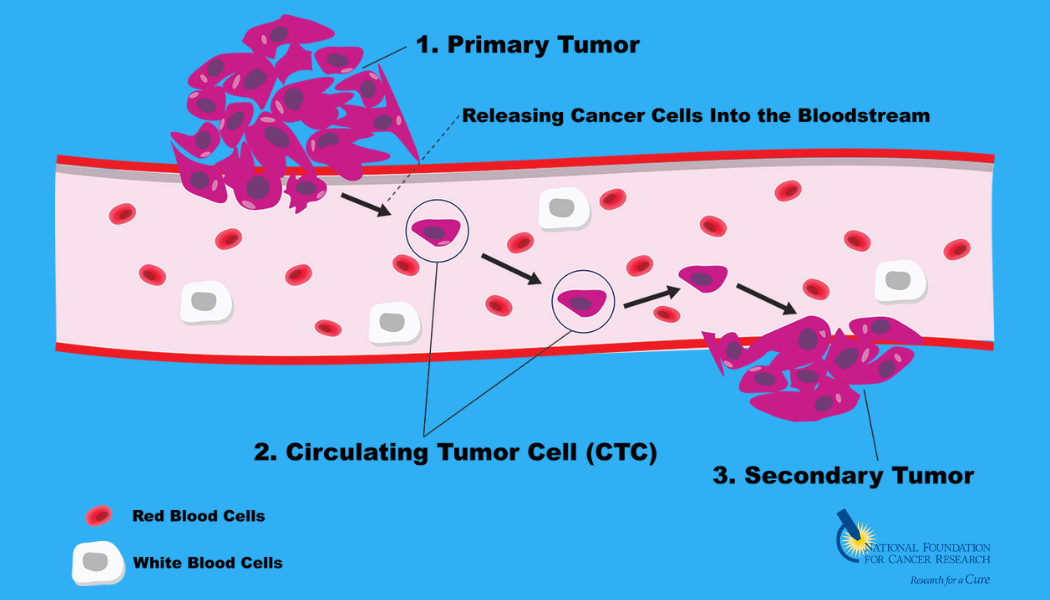

As a next step toward developing this compound as a new cancer drug, Dr. Kelliher’s team will test its ability to stop growth of circulating tumor cells (CTCs) isolated directly from multiple myeloma patients using the advanced cancer cell detection technology.